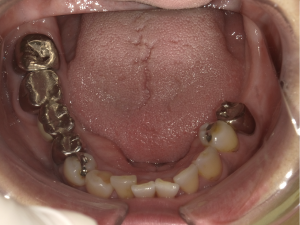

インプラント治療(左上5ソケット・GBR 右上2左上13GBR)

| 年代・性別 | 50代・男性 |

|---|---|

| 主訴 | 入れ歯だと咬めなくてつらい。 |

| 部位 | 上顎②1①2③4⑤Br |

| 治療期間 | 約9ヶ月 |

| 費用 | ¥1,794,100(税込) |

| 副作用・リスク |

|